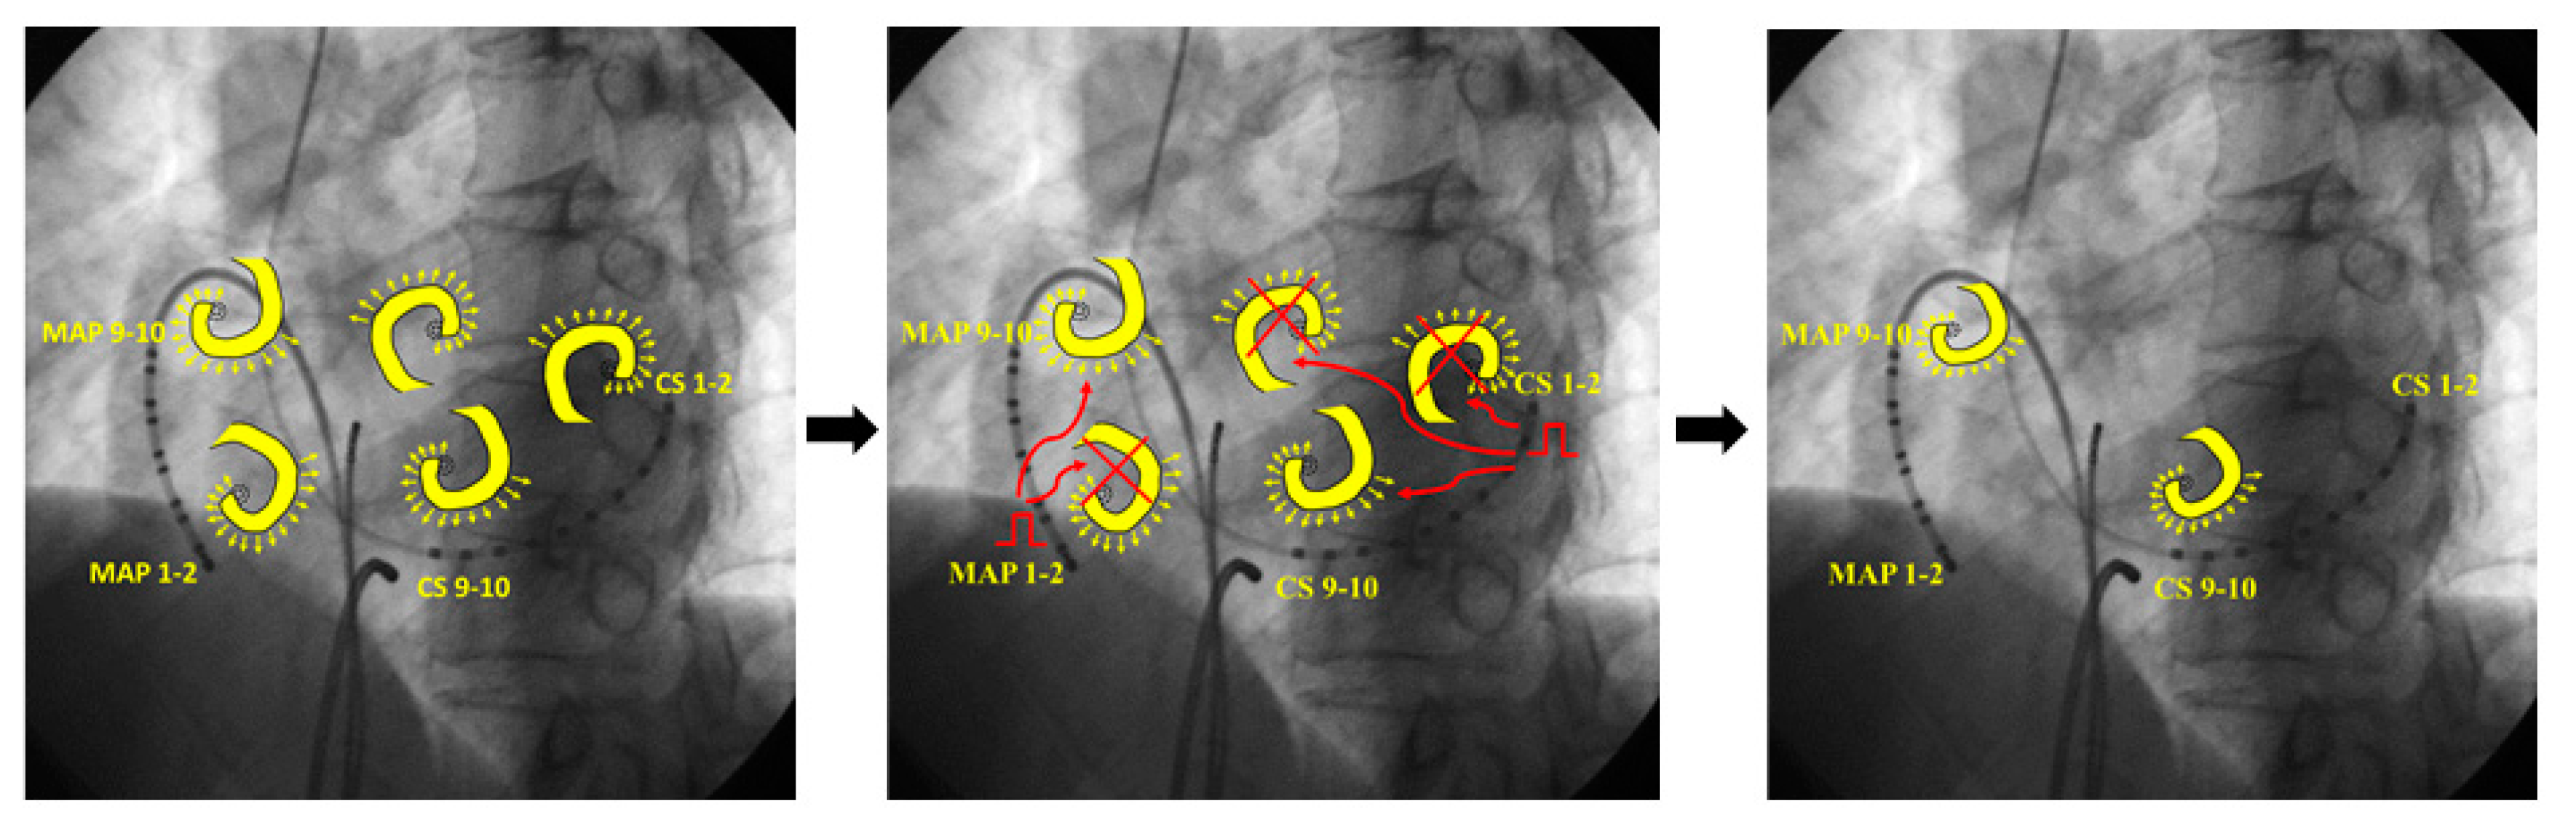

4.1. Mechanism of AF Termination

- (A)

- (B)

- (C)

- Leading circle theory [14]; The presence of an excitable gap is well known for the maintenance of AF. Pacing stimuli entrain and fill the excitable gaps of tachycardia, affecting the refractory period. Eventually, AF is unable to sustain itself and thus terminates slowly.